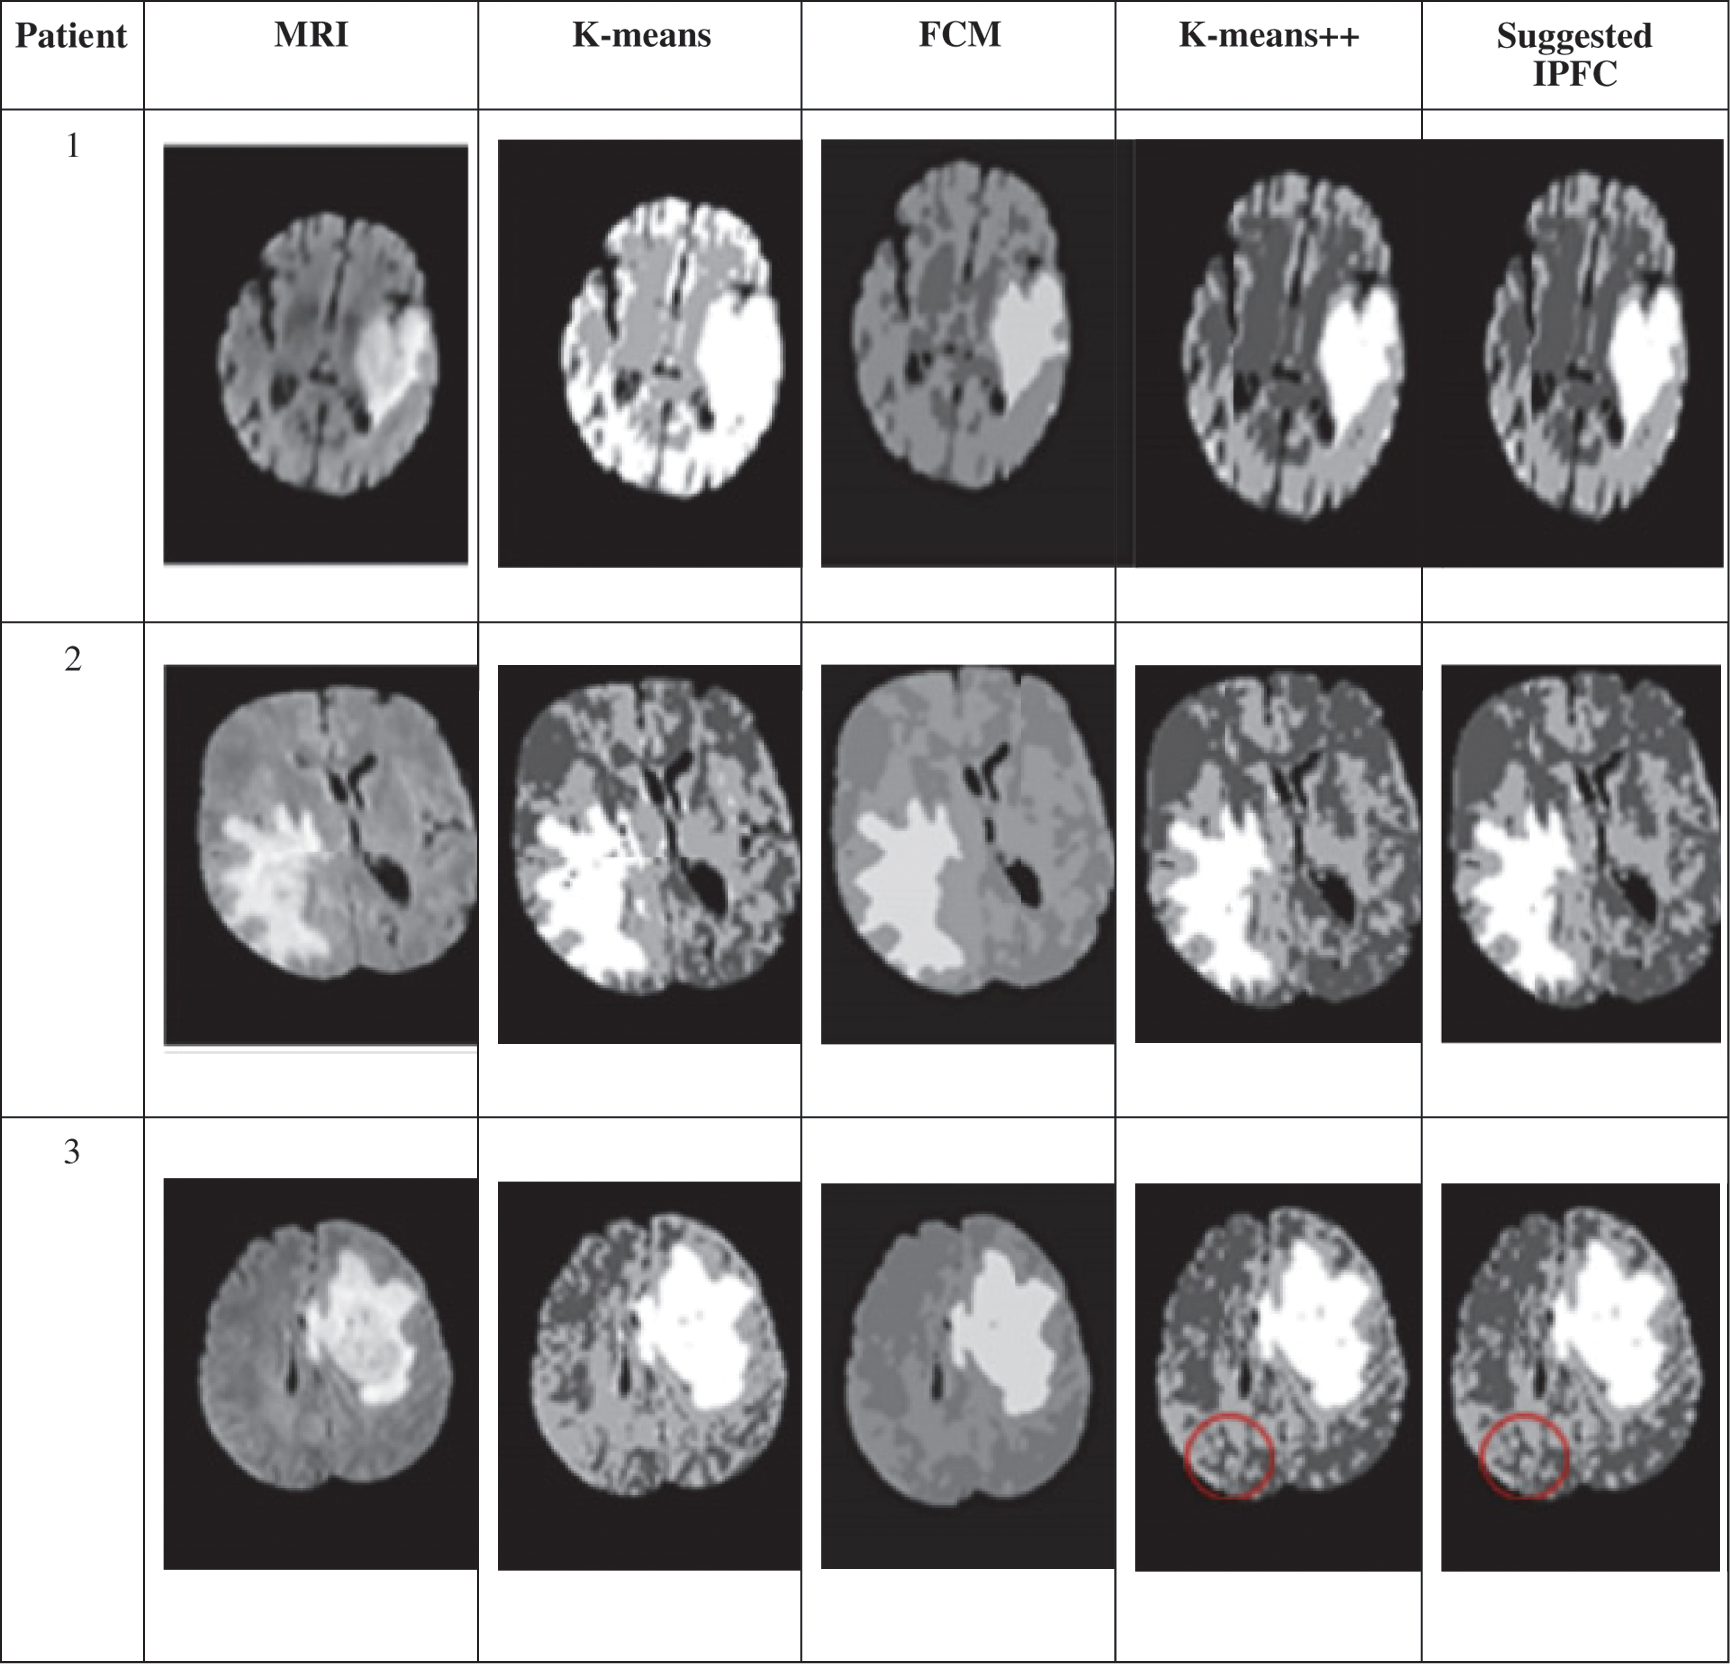

A. Comparison with Some Recently Proposed Clustering Algorithms

The anticipated method efficacy is assessed through comparison of various contemporary clustering algorithms. For analysis purpose, the random selection of tree brain MR images is performed. The suggested algorithm clustering efficiency and its performance comparison with regard to FCM, K-means group are depicted in Fig. 6. Accordingly, clearly exhibited algorithm proposed in this study has high accuracy than other algorithms in terms of texture details handling.

Figure 6: Clustering outcomes of K-means, FCM, K-means++methods, suggested IPFC clustering method

For instance, individual brain images belongs to three different patients have been considered in this study as samples. Consequently, recommended IPFC algorithm comparison is done with three different clustering algorithms, namely K-means, FCM and K-means++ algorithms, which is depicted in Tab. 2 The numerical outcomes represent that suggested algorithm has maximum values with regards to Dice, Sensitivity, and Specificity parameters.